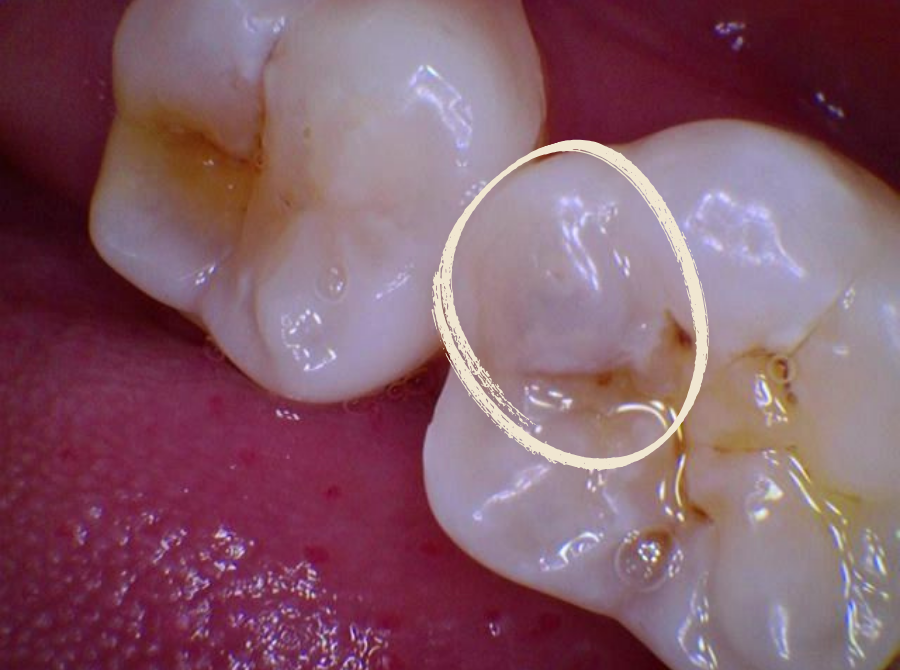

• A visible hole or dark spot on a tooth

However, cavities can also develop with no noticeable symptoms.

A dental examination and X-ray remain the most reliable ways to assess whether a filling is required.